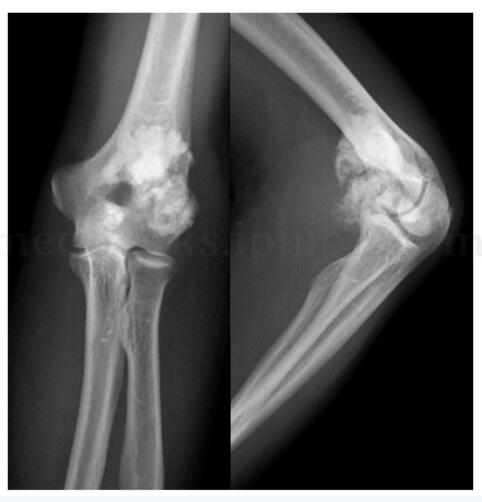

影像学检查:X 线片(图8‐3)和CT(图8‐4)表现为左肘关节前方偏肱骨远端左侧可见类圆形高密度肿块影,边界尚清,与肱骨远端骨皮质间尚有间隙。MRI(图8‐5)表现为左肱骨远端前侧类圆形混杂T 1、混杂T 2信号灶,边界较清,大小约3cm ×3cm ×3cm,增强后呈中度不均匀强化,肱骨远端髓内及前缘骨皮质可见片状低T 1、低T 2信号灶。全身骨扫描(99m Tc‐MDP)(图8‐6)显示为左肱骨远端异常放射性浓集、全身其他部位未见异常放射性浓聚。

图8‐3 X 线片(正侧位)表现

此例患者为老年男性,但自青年期起病,病史较长,症状以关节活动受限为主,存在慢性滑膜炎症状,临床上符合诊断标准Ⅲ(b)。X 线及CT 显示类圆形高密度肿块影,边界尚清,与肱骨远端骨皮质间尚有间隙,影像学符合Ⅱ(b)。故本病应高度疑诊二水焦磷酸钙沉积病。术后病理证实该病诊断。